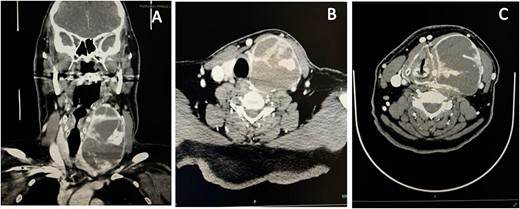

Laboratory investigations showed a normal basic profile and normal thyroid function tests. An urgent contrasted computed tomography (CT) of the neck revealed a large left complex solid and cystic thyroid lobe lesion, measuring 6 × 6.6 × 10.3 cm, with retrosternal extension, exerting a mass effect on the trachea causing a shift to the right side. Multiple hyperdense nodularities were seen within the lesion, which could represent intralesional blood products, calcification, or active extravasation. The hyperdense component was evident on contrasted soft tissue window but not on the bone window, suggesting a hemorrhagic thyroid nodule. The lesion abutted the left common carotid artery with lateral displacement and compression of the left jugular vein. No suspicious necrotic lymphadenopathy, central airways patent, and no destructive bone lesions were appreciated (Fig. 2).

Neck CT scan revealed diffusely enlarged complex cystic and solid thyroid nodule compressing the trachea causing shift to the right side. (A) Coronal view. (B, C) Axial view.